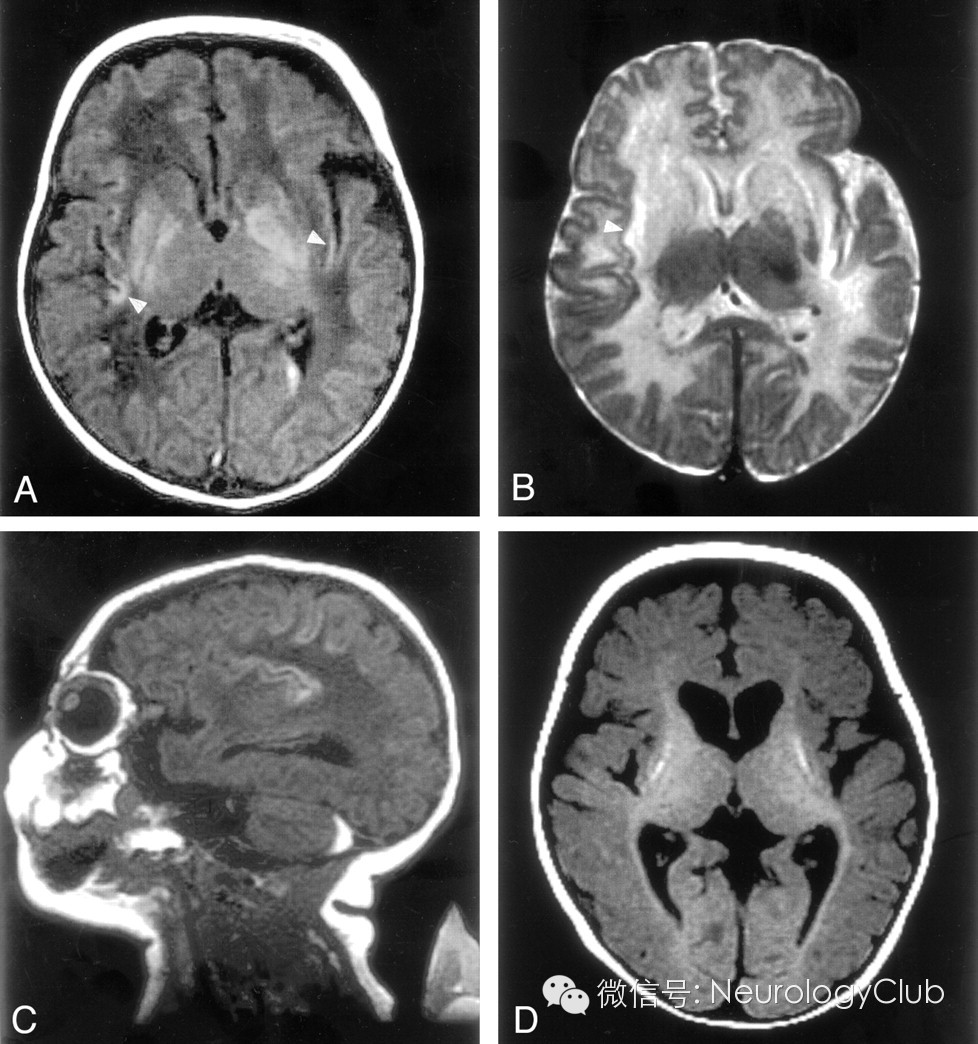

病例3

2周患儿,女性。

(A:T1WI示双侧豆状核[苍白球较壳核更明显]及岛叶皮层高信号;左侧脑室内出血;B:T2WI示左侧苍白球低信号,双侧纹状体及近岛叶白质高信号;C:T1WI示岛叶和中央颞区深部脑沟高信号,小脑后部硬膜下血肿;D:7月大时,T1WI示基底节区体积减少,壳核高信号,脑白质体积减少,弥漫皮层萎缩,内囊后肢和视辐射区可见髓鞘形成)